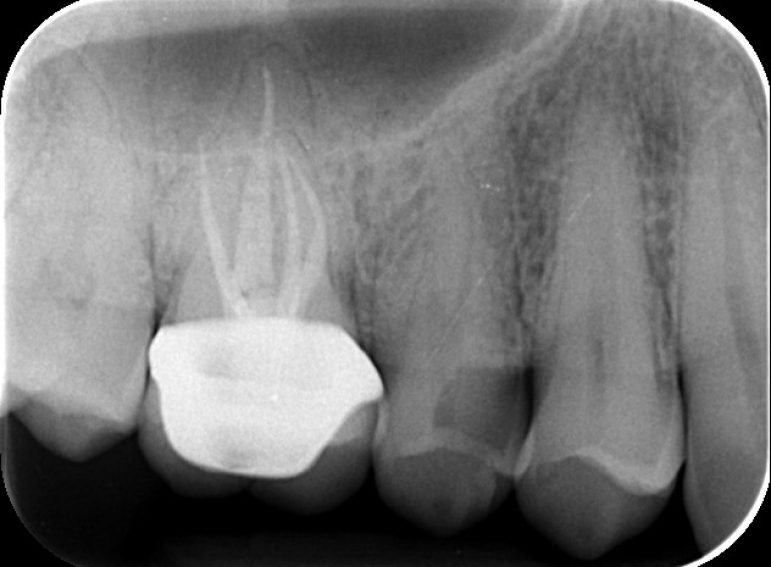

composite restoration of a cavity on lower left molar due to an impacted wisdom tooth.